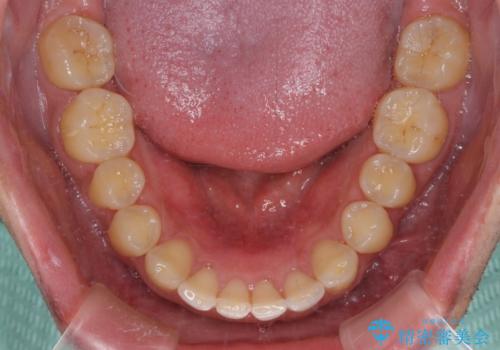

- 上顎前歯の突出感とすきっ歯を気にして来院された患者様です。

奥歯の咬み合わせを見ると、下顎に対して上顎が前方に位置していたため、補助装置により上顎歯列全体を後方に移動させ、その後インビザラインにて歯列全体を整えることとしました。